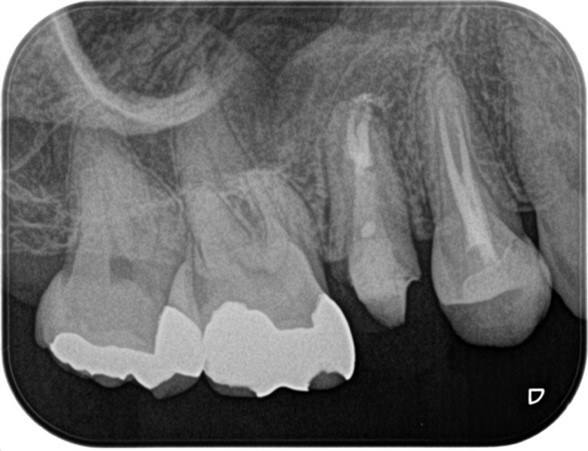

精密根管治療終了後、3ヶ月間仮歯で症状の経過を確認し、予後良好と判断して最終補綴物へ移行しました。

経過2年の段階で根尖に確認できた根尖性歯周炎は縮小し、予後良好の経緯を確認しています。